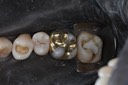

Mark Chun #19 casting